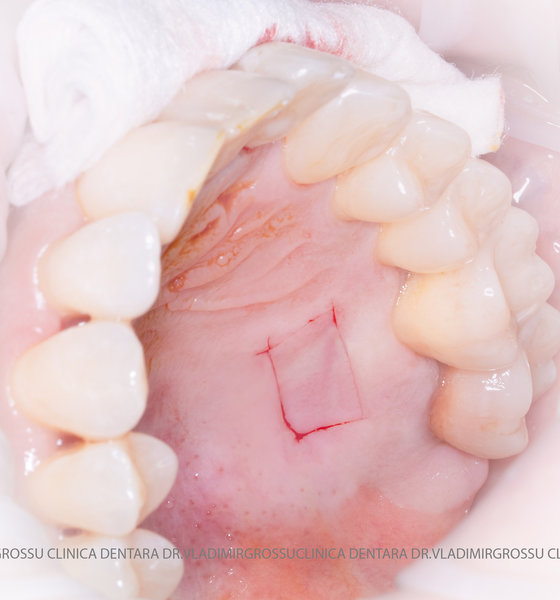

Un element esențial în procedura de aditie osoasă este utilizarea membranelor biologice, care izolează materialul osos de țesuturile moi (gingie) pe durata procesului de vindecare. Cele mai recomandate sunt membranele resorbabile din colagen sau pericard.

Adiția de gingie (gingivoplastia)

Aditia gingivală este o procedură chirurgicală ce corectează diverse probleme estetice și funcționale, cum ar fi recesiunea gingivală. În implantologia modernă, aditia de țesut moale este utilizată aproape în fiecare intervenție de inserție a implantului dentar pentru a asigura un aspect estetic natural și o bună integrare a implantului în cavitatea bucală.